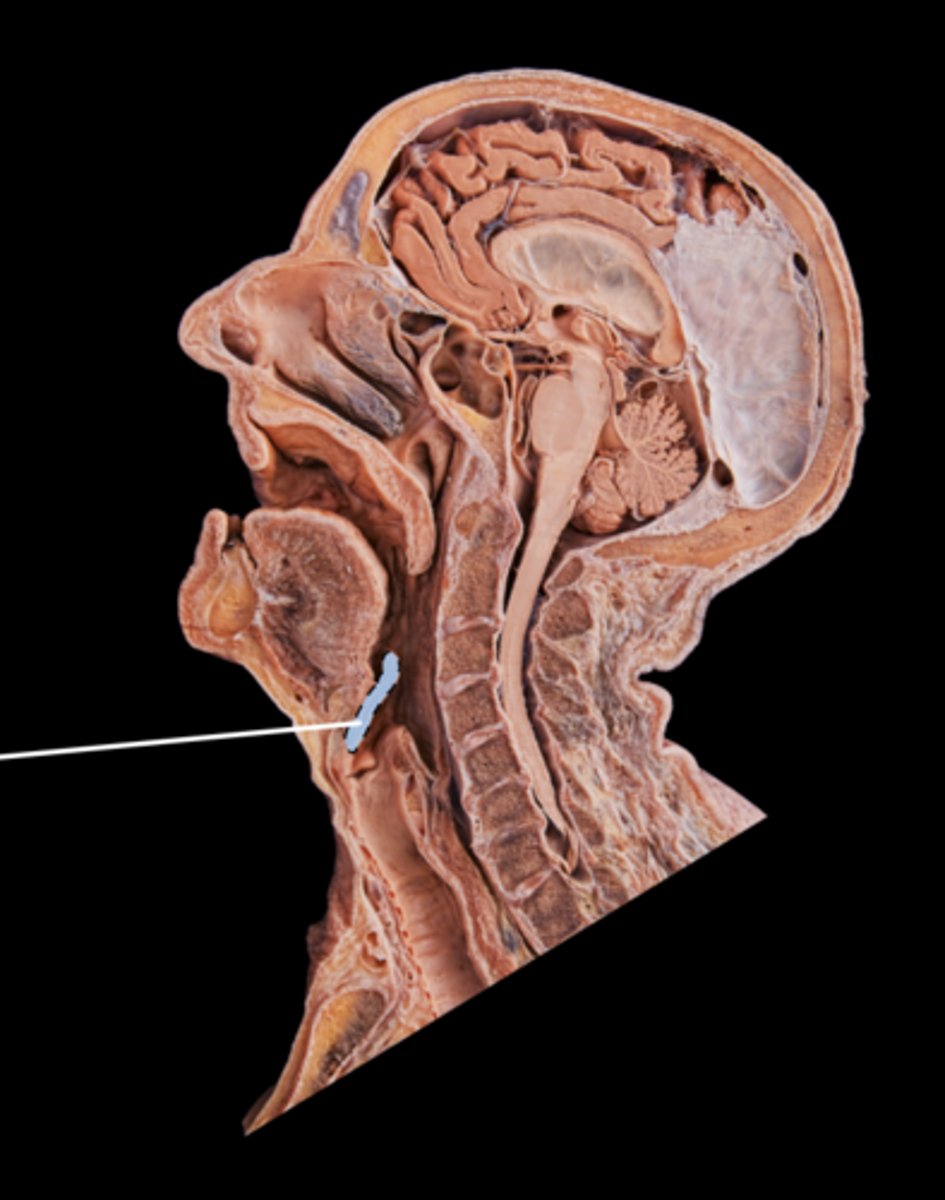

Tongue

Lingual Tonsil

Palatine Tonsil

Esophagus

Parotid Salivary Gland

Submandibular Salivary Gland

Epiglottis